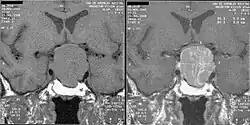

W ciągu pierwszych trzech dni udaru przysadka oraz okolice powyżej niej są hiperdensyjne na obrazach bez kontrastu, co utrudnia różnicowanie z tętniakiem okołoprzysadkowym (w rozróżnianiu czulsze jest MRI)[6]. Po pewnym czasie hiperdensyjność zanika, a TK zmniejsza swoją czułość w rozpoznawaniu udaru, wówczas udar może być trudny do odróżnienia od ropnia lub torbieli[6].